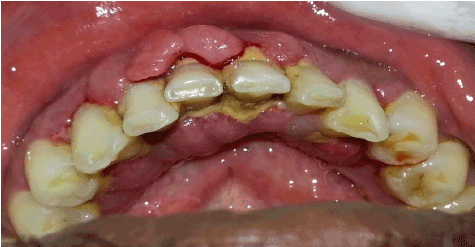

口腔内检查显示口腔卫生差,菌斑评分和牙石评分高,下前牙面、舌侧牙龈结节状增大(图1、2)。牙龈增大累及边缘、乳头状及附着龈。牙龈发炎,质地柔软,多处自发性出血。病人由于生长过快,说话和咀嚼有困难。根据1999年Eva Ingles关于牙龈过度生长的临床指标[4],将牙龈过度生长分为III级(明显过度生长,表现为牙龈侵犯临床冠,牙龈边缘轮廓凸出,颊舌尺寸约为3mm或以上)。探测袋深度大于6mm,乳头可伸缩)。

图1:第一阶段治疗前牙龈发炎、肿大

图2:I期治疗前的切牙视图